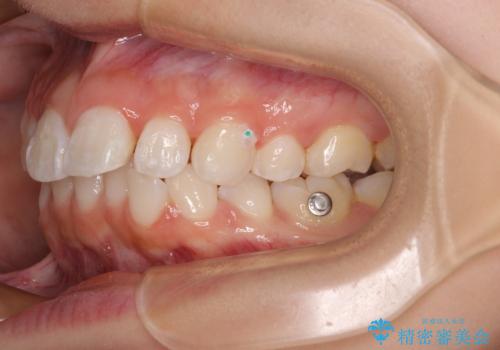

- 上下前歯の叢生を気にして来院された患者様です。

インビザラインでの治療を希望されていて、デコボコの程度が中等度であり、安価なパッケージにて対応可能と判断されたため、インビザライン・モデレートを用いて矯正治療を行うこととしました。